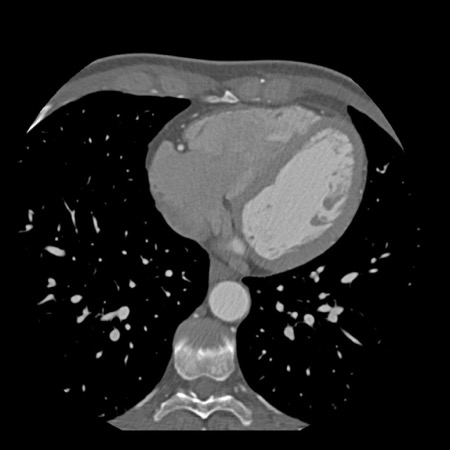

case 1 – CAD-RADS 2/P1

First, scroll through the scan.

Not all images are included. Some images without any abnormalities are skipped

from the series.

How would you describe the findings on the coronary CTA?

The findings are:

- Agatston score of

this patient was 14 (P1). Please, also note the calcification of the aortic valve. - Some partially

calcified and calcified plaques are present in the LAD with mild stenosis

(25-49%). - Calcified-plaque in

the LCX causing minimal stenosis (<25%). - Non-calcified

plaque in the distal RCA causing minimal stenosis (<25%). - This patient classifies

as CAD-RADS 2/P1, which means no further workup is needed.